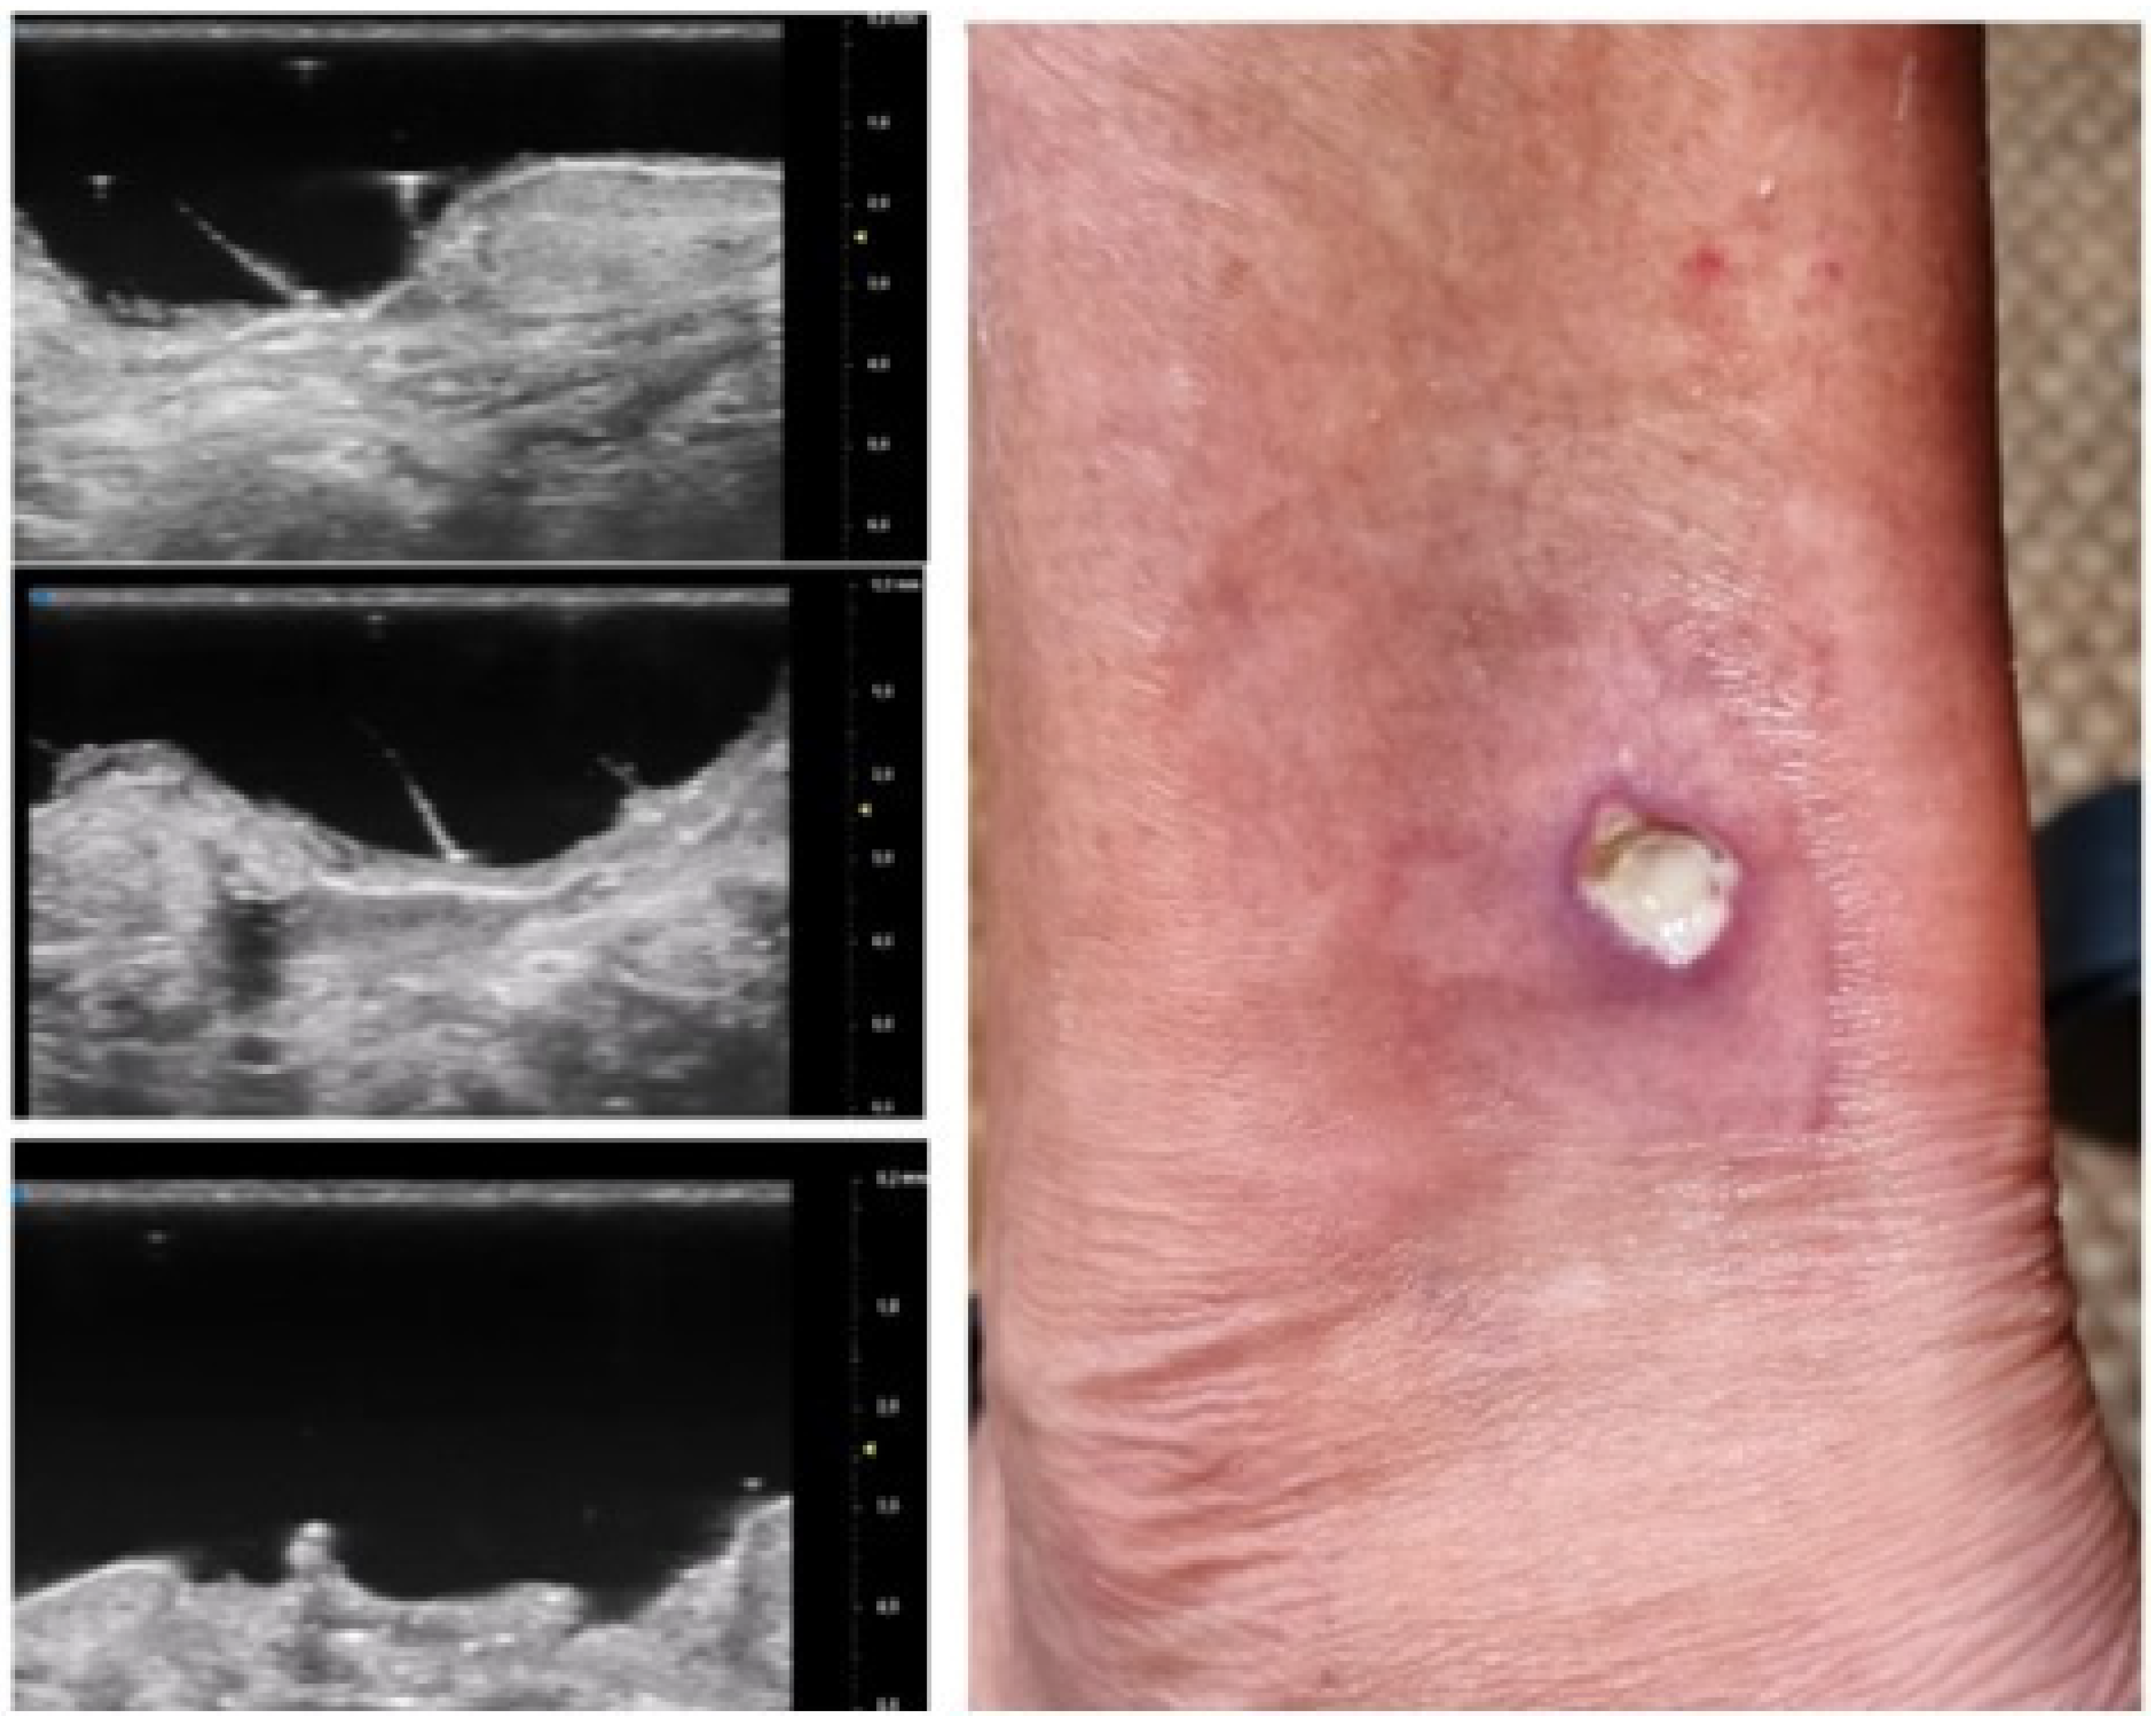

Figure 6.

Early PG lesion: the purulent material (included by the black line) is well demarcated and undermined from the surrounding dermis giving a wave-like appearance, the so-called “tsunami sign”.

Moreover, the presence of similar UHFUS findings between the pustular and ulcerative phenotypes in T0, suggested the idea, not yet confirmed in the literature, that the pustular phenotype was an early stage of the ulcerative one, in agreement with the assumption of Powell et al. this hypothesis could be supported by our population’s anamnestic data that reveal a clinical onset with confluent or non-confluent pustules in 5 patients. (Figure 7) [12].

Figure 7.

UHFUS PG features: early PG pustule with hair tract (A1-2-3); undermined purulent material with the “tsunami sign” formation (B1-2-3); PG evolution toward ulceration (C1-2-3); PG lesion during non-inflammatory phase (D1-2-3); healed PG lesion (E1-2).